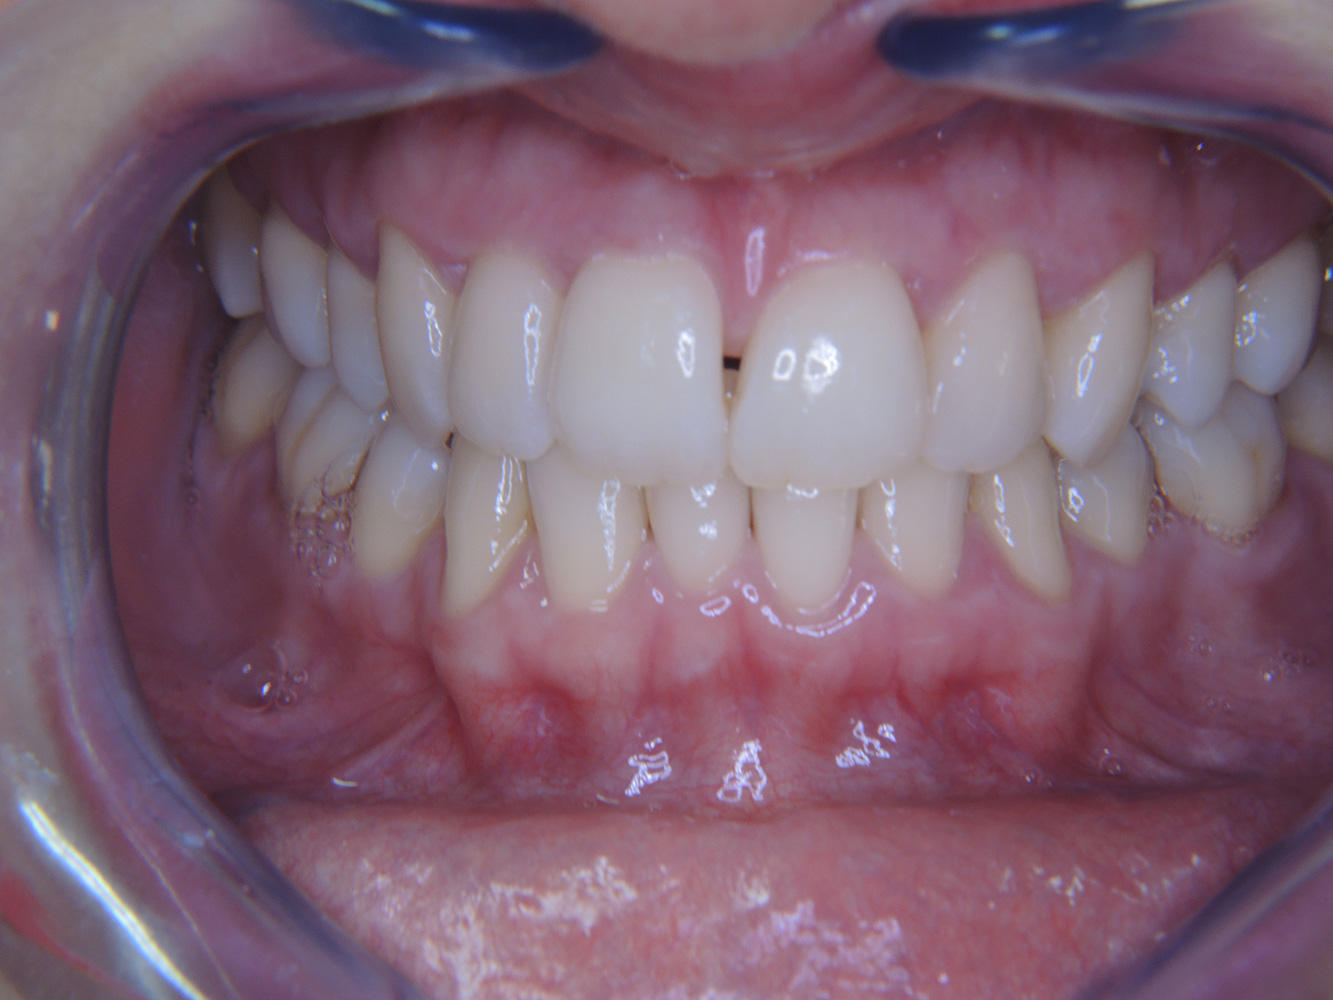

The (orally) healthy patient with implants

In the medical history, the 55-year-old patient states that he has no systemic disease and is not taking any medication. The patient’s lifestyle is similarly unremarkable. The patient has a few tooth restorations and two implants (2nd and 4th quadrants). On the basis of current findings, gingivitis is identified in an otherwise stable periodontal condition on the reduced periodontium (stage III, grade A). more